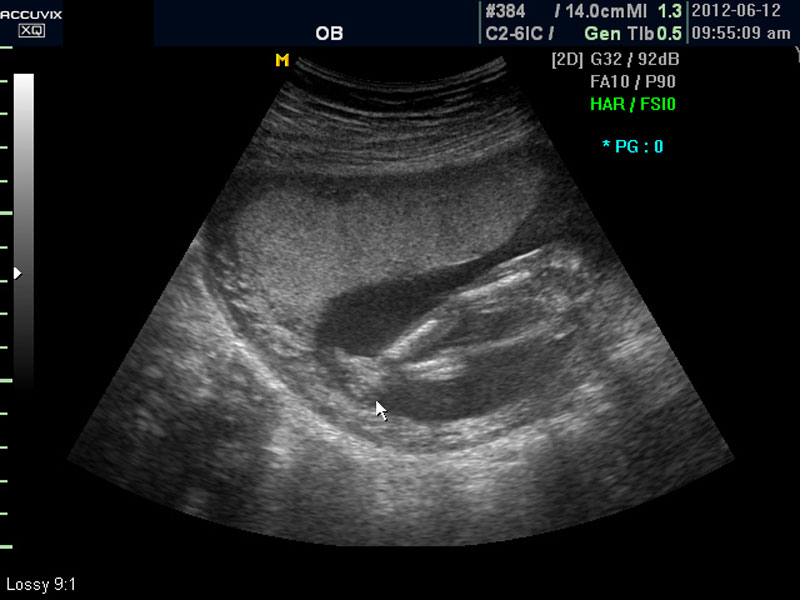

임신 중기의 초음파에서는 아기의 크기, 심장 박동이나 활동의 정도, 각종 장기의 구성이 정상인가 하는 것을 살펴 보게 됩니다.

대신 첫번째 사진에서 보는 것처럼 태아의 전체 모습 특히 태아의 등쪽이나 복벽의 이상은 없는지 신경관 결손 등으로 인한 종괴가 있지는 않은지 관찰하며 태아의 복벽이나 등쪽은 일직선으로 매끈하게 보이는 것이 정상입니다.

첫번째 사진에서는 하지 부분은 대퇴부만 일부 보이며 이는 태아가 다리를 구부리고 있고 팔도 이리저리 움직여 머리 위나 목 쪽으로 두는 경우가 많아서 한번에 전체 모습을 찍기가 어려운 경우가 많습니다.

화면에서는 위쪽에 하얗게 균일하게 보이는 것이 태반의 모습입니다.

태반은 실제로 보면 피자처럼 둥그런 원판 모양이며 임신 후기로 갈수록 태아와 마찬가지로 크기가 커지고 두꺼워집니다.

사진에서 검게 보이는 것이 양수입니다. 양수에 대하여는 색깔이나 밀도 등 다른 요소는 알기 어려워서 그 양만 가지고 판단을 하게 됩니다.